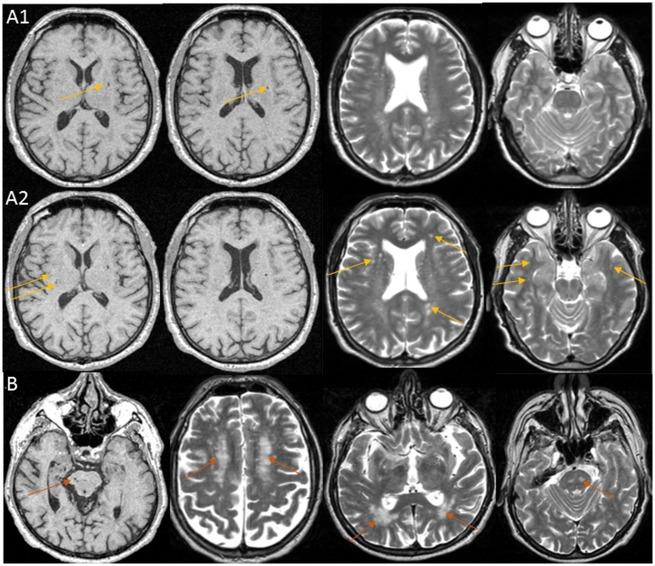

We report a composite extreme phenotype design using distribution of white matter hyperintensities and brain infarcts in a population-based cohort of older persons for gene-mapping of cerebral small vessel disease. We demonstrate its application in the 3C-Dijon whole exome sequencing (WES) study (n = 1924, nWESextremes = 512), with both single variant and gene-based association tests. We used other population-based cohort studies participating in the CHARGE consortium for replication, using whole exome sequencing (nWES = 2,868, nWESextremes = 956) and genome-wide genotypes (nGW = 9924, nGWextremes = 3308). We restricted our study to candidate genes known to harbour mutations for Mendelian small vessel disease: NOTCH3, HTRA1, COL4A1, COL4A2 and TREX1. We identified significant associations of a common intronic variant in HTRA1, rs2293871 using single variant association testing (Pdiscovery = 8.21 × 10-5, Preplication = 5.25 × 10-3, Pcombined = 4.72 × 10-5) and of NOTCH3 using gene-based tests (Pdiscovery = 1.61 × 10-2, Preplication = 3.99 × 10-2, Pcombined = 5.31 × 10-3). Follow-up analysis identified significant association of rs2293871 with small vessel ischaemic stroke, and two blood expression quantitative trait loci of HTRA1 in linkage disequilibrium. Additionally, we identified two participants in the 3C-Dijon cohort (0.4%) carrying heterozygote genotypes at known pathogenic variants for familial small vessel disease within NOTCH3 and HTRA1. In conclusion, our proof-of-concept study provides strong evidence that using a novel composite MRI-derived phenotype for extremes of small vessel disease can facilitate the identification of genetic variants underlying small vessel disease, both common variants and those with rare and low frequency. The findings demonstrate shared mechanisms and a continuum between genes underlying Mendelian small vessel disease and those contributing to the common, multifactorial form of the disease.

我们报告了一种基于人群的老年人队列的脑白质高信号和脑梗死分布的复合极端表型设计,用于大脑小血管疾病的基因定位。我们展示了它在 3C-第戎全外显子组测序(WES)研究(n = 1924,nWESextremes = 512)中的应用,包括单变体和基于基因的关联测试。我们使用参与 CHARGE 联盟的其他基于人群的队列研究进行复制,使用全外显子组测序(nWES = 2,868,nWESextremes = 956)和全基因组基因型(nGW = 9924,nGWextremes = 3308)。我们将研究限制在已知携带孟德尔小血管疾病突变的候选基因中:NOTCH3、HTRA1、COL4A1、COL4A2 和 TREX1。我们使用单变体关联测试发现 HTRA1 中的一个常见内含子变体 rs2293871 具有显著关联(Pdiscovery = 8.21 × 10-5,Preplication = 5.25 × 10-3,Pcombined = 4.72 × 10-5),并使用基于基因的测试发现 NOTCH3 具有显著关联(Pdiscovery = 1.61 × 10-2,Preplication = 3.99 × 10-2,Pcombined = 5.31 × 10-3)。后续分析确定 rs2293871 与小血管缺血性卒中显著相关,以及与 HTRA1 连锁不平衡的两个血液表达数量性状基因座。此外,我们在 3C-第戎队列中发现了两名参与者(0.4%)携带 NOTCH3 和 HTRA1 中家族性小血管疾病已知致病性变异的杂合基因型。总之,我们的概念验证研究提供了强有力的证据,表明使用新型复合 MRI 衍生表型来研究小血管疾病的极端情况可以促进鉴定小血管疾病的遗传变异,包括常见变异和罕见和低频变异。这些发现表明孟德尔小血管疾病相关基因与导致常见多因素疾病的基因之间存在共同机制和连续体。